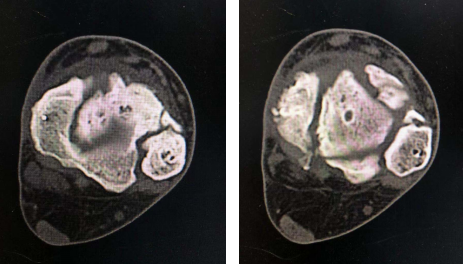

术前体表(左图)术前X线(右图)

术前CT